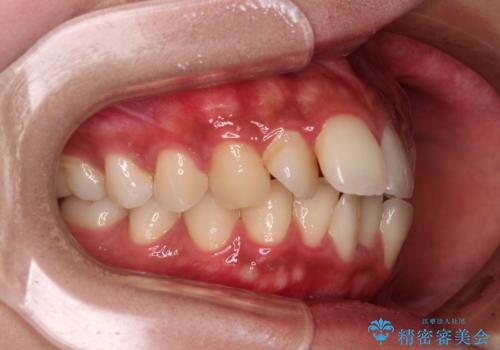

奥歯の噛み合わせをみると、上顎歯列が全体的に前突している状態であり、この咬み合わせのまま歯列を整えると出っ歯になってしまう可能性がありました。

アンカースクリューと補助装置を使用して上顎大臼歯を遠心移動させることで咬み合わせを改善し、更には口元の突出感を改善するために上下左右の小臼歯4本を抜歯し、ワイヤー装置によりデコボコを解消しながら口元の突出感も改善していくこととしました。

上下の前歯が接触する仕上がりとなったので、横顔の印象が大幅に改善されました。